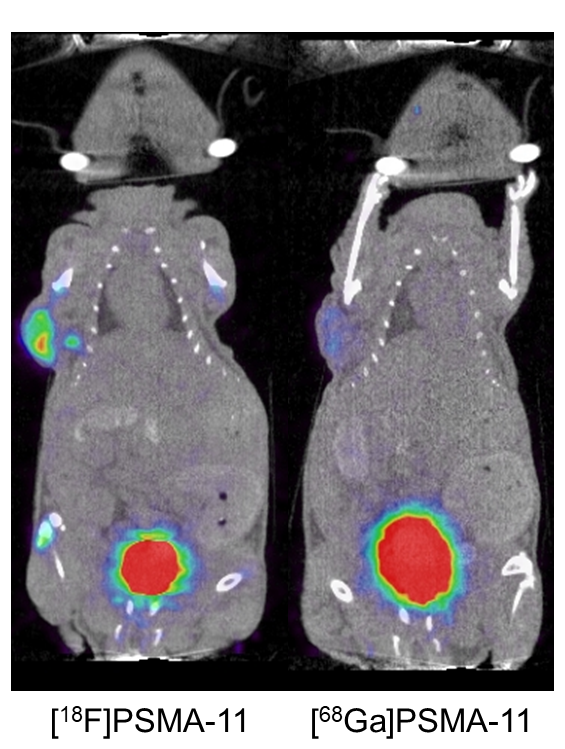

Comparison of Ga68-PSMA and F18-PSMA in clinical and preclinical studies.

Prostate-specific membrane antigen (PSMA) is highly overexpressed in prostate cancer. Many PSMA analog radiotracers for PET/CT prostate cancer staging have been developed, such as 68Ga-PSMA-11. This radiotracer has achieved good results in multiple clinical trials, but because of the superior imaging characteristics of 18F-fluoride, 18F-PSMA-11 was developed. The aim of this study is to compare the prostate‐specific membrane antigen (PSMA)‐targeting characteristics of PSMA‐11, radiolabeled based on chelation of 18F‐AlF, to those of 68Ga‐PSMA‐11 to image PSMA‐expressing xenografts.